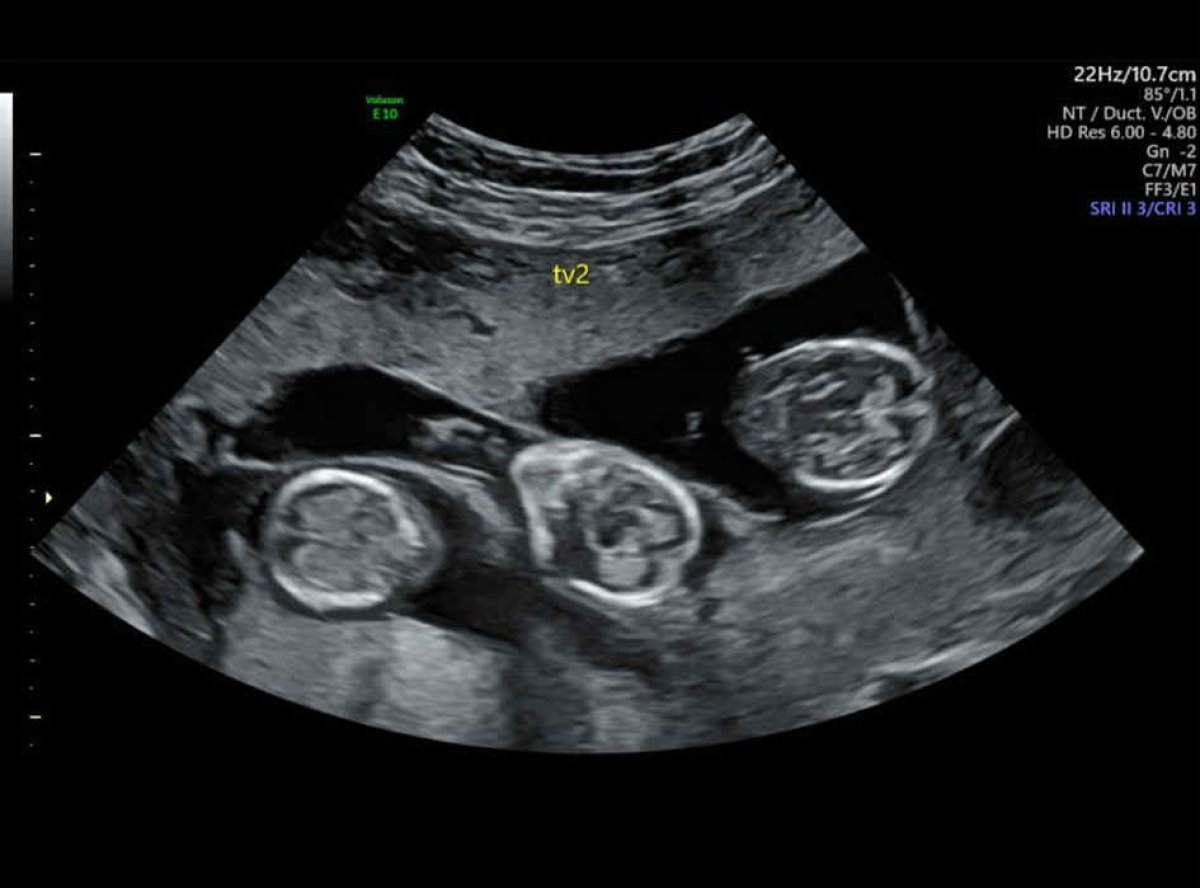

Šveđanka Mari Gustavson (50) je uprkos prognozama lekara osam meseci nakon vantelesne oplodnje na svet donela trojke, sina Čarlija i ćerke Lorin i Laru.

S obzirom na godine, nisu očekivali brz uspeh, pa su tokom procedure preneta tri embriona kako bi povećali šanse. Iako su ih lekari upozoravali na rizike i savetovali redukciju, Mari je odlučila da veruje svom osećaju. Na kraju su se primila sva tri embriona.

Lečenje su obavili na Kipru i platili oko pet hiljada i petsto evra, a pozitivan test dobili su svega tri dana nakon transfera. Trudnoća je bila izazovna,kako kaže, stomak joj je bio toliko zategnut da gotovo nije osećala pokrete beba.

Trojke su rođene hitnim carskim rezom, što je bila jedina razlika u odnosu na prethodne porođaje koje je imala prirodnim putem. Dečak je imao 1,5 kilogram, jedna devojčica 1,3, a druga samo kilogram.